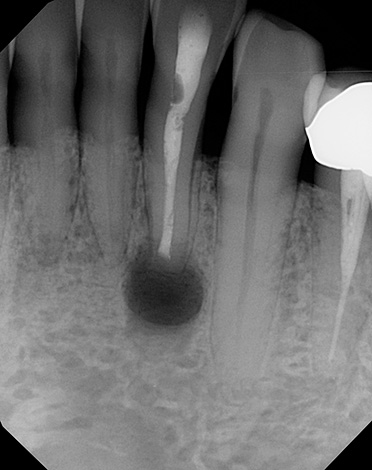

A foto abaixo mostra um exemplo de dente removido com cistos nas raízes:

É difícil determinar com uma imagem objetiva e mesmo com uma tomografia computadorizada com 100% de precisão que forma do processo inflamatório está presente na (s) raiz (s) do dente. Área de iluminação geralmente visível com contornos claros, geralmente arredondados ou ovais. Esse "círculo" pode ser localizado não apenas em uma raiz, mas também captura 2-3 raízes de um dente e até mesmo passa nas proximidades imediatas do topo das raízes dos dentes adjacentes, sugerindo ao dentista a escala da tragédia.